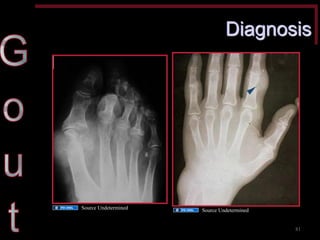

Diagnosis •Rule out cellulitis, septic arthritis particularly if knee joint •All may have fever, leukocytosis, elevated ESR •Uric acid level not helpful •X-rays: soft-tissue swelling (acute) or joint destruction (chronic)

Diagnosis

Source Undetermined

Diagnosis •Definitive diagnosis: birefringent joint fluid crystals with polarizing microscope (a yellow crystal against a red background) and negative joint fluid culture